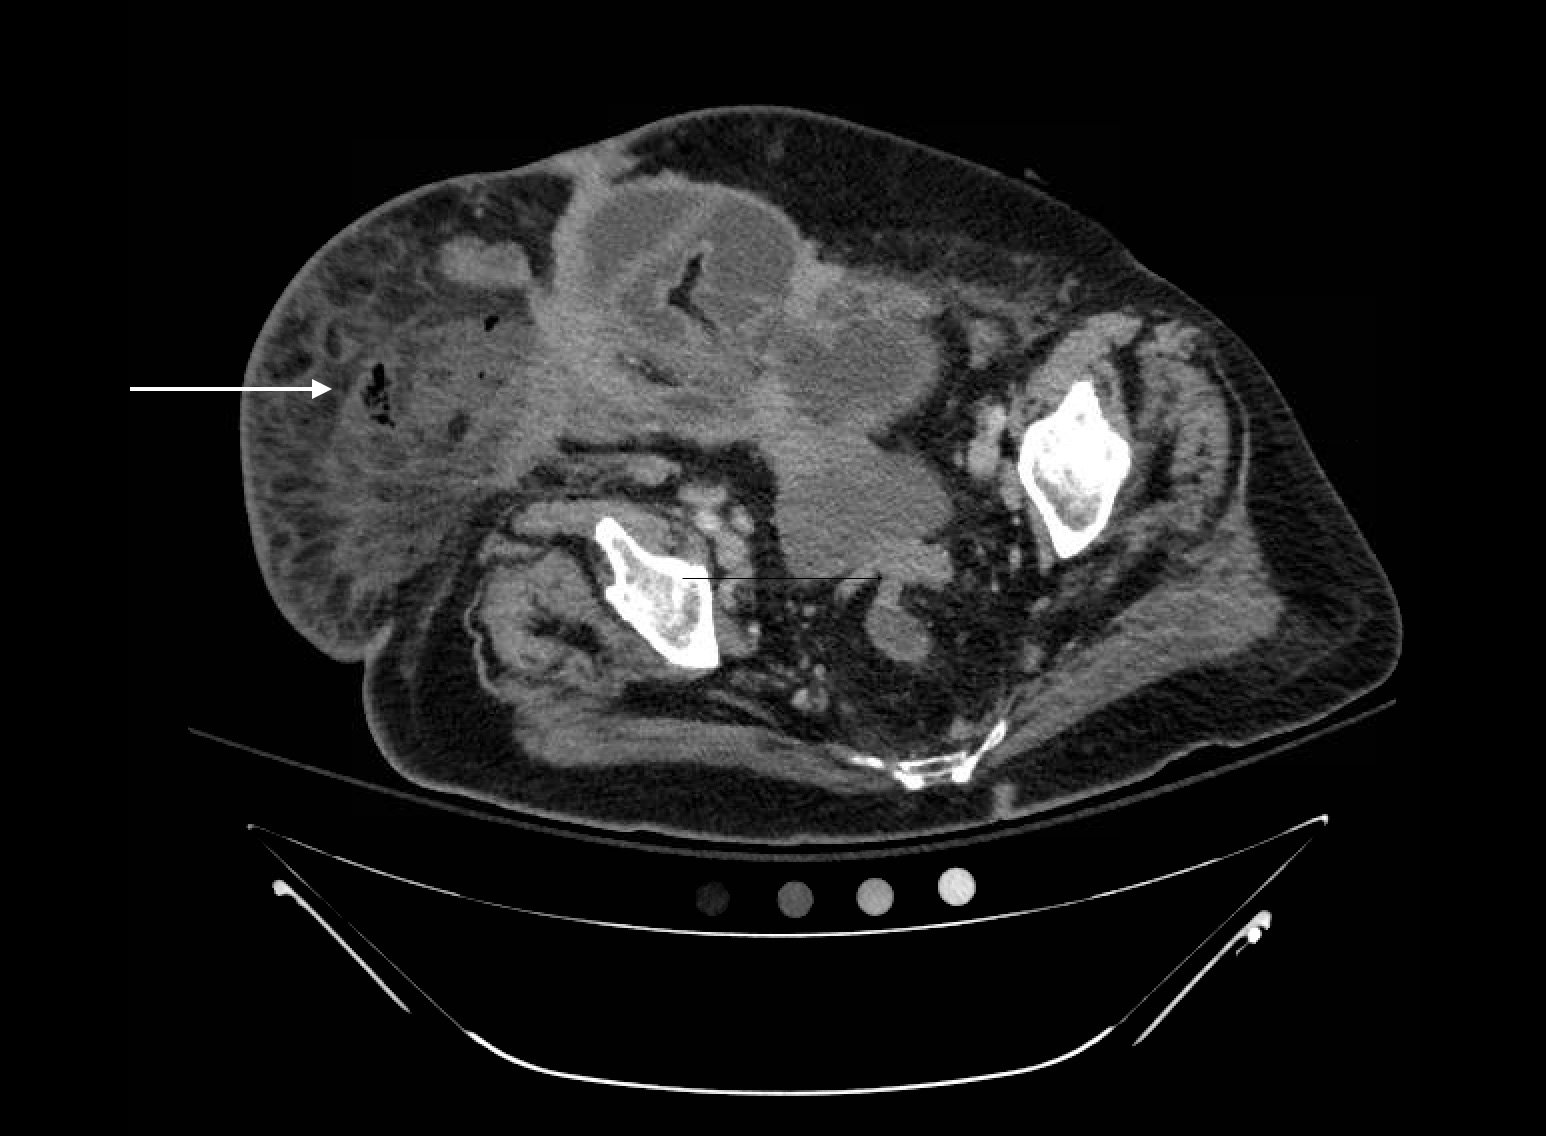

Computed tomography (CT) of the abdominal and pelvis with intravenous (IV) contrast revealed inflammatory changes, including gas and fluid collections within the ventral abdominal wall extending to the vulva, consistent with a necrotizing soft tissue infection.